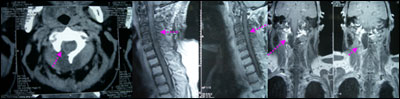

科内讨论认为,肿瘤大部分位于硬膜外,可考虑半椎板入路,在全切肿瘤的情况下不影响颈椎的稳定性,术中见肿瘤大部位于硬膜外,肿瘤和C1-2神经节关系密切,硬膜下的神经成团聚集并变性增粗,毗邻的蛛网膜变性肥厚。肿瘤血运丰富,毗邻椎动脉和周围的椎静脉丛。

术后图片:

专家评点:对于脖子短粗,颈项肌肉发达的患者,半椎板切除肿瘤对术者来说是一个挑战,尤其是碰到血运丰富的肿瘤,要求术者对入路解剖结构非常熟悉,而且镜下操作也应相当娴熟。才能不损伤正常结构的情况下,全切肿瘤。